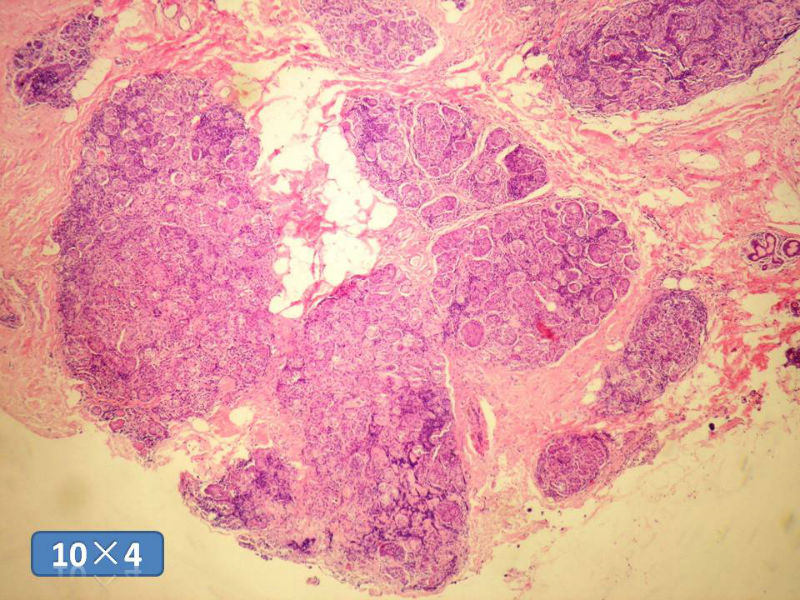

女性,50岁,乳腺肿物,冰冻切片(图1-25)

HE